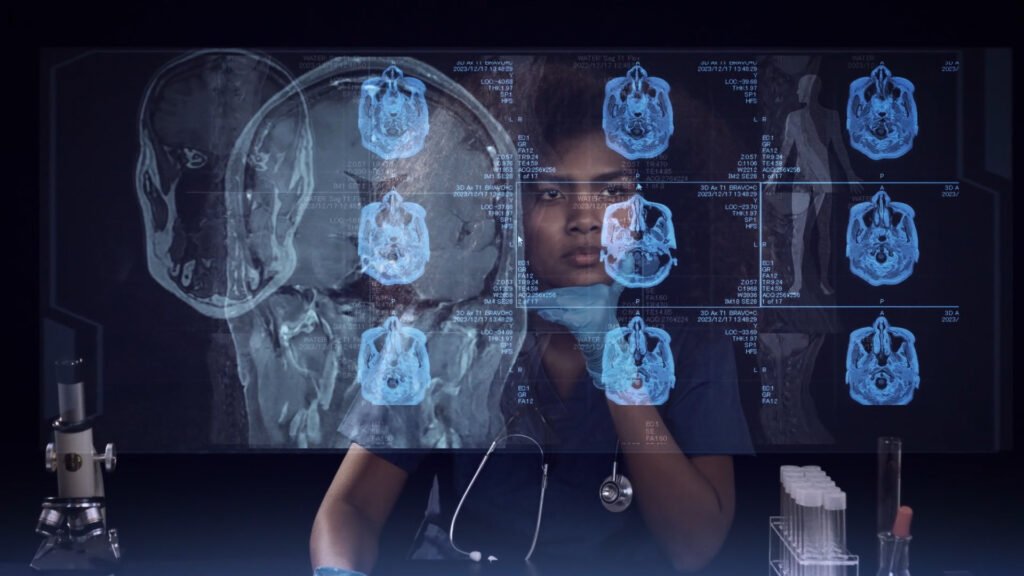

We crafted a dynamic project video for Citeline Clinical, showcasing how their AI-driven solutions are transforming clinical trials. This life-saving technology is setting a new standard in medical innovation.